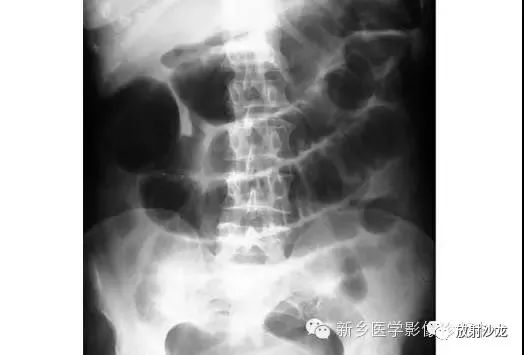

腹部平片解剖

腹部脏器有实质器官和空腔脏器之分,其正常腹平片表现不同。

● 腹平片上实质器官的正常表现:

实质器官:肝、胰、脾和肾等是中等密度,但借助于器官周围或邻近的脂肪组织和相邻充气肠胃的对比,于腹平片上,可显示器官的轮廓、大小、形状及位置。

正位片在部分病人可显示肝下缘,肝下缘与肝外缘相交形成肝角,一般呈锐角。

脾上极与左膈影融合,下极较圆钝。而肾沿腰大肌上部排列。

胰腺于平片上不易显示。子宫偶尔显影,位于膀胱上缘上方呈扁圆形软组织影。

● 空腔脏器在腹平片上的主要表现:

空腔器官:膀胱的脏壁为中、胆囊和肠胃道等密度,依腔内容物不同而x线表现不同。

胃、十二指肠球部及结肠内可含气体,于腹平片上可显示其内腔。小肠除婴幼儿可有积气外,一般充满食糜及消化液,与肠壁同属中等密度,因缺乏对比而不能显示。

如胃内有较多固态食物,结肠或直肠内有较多粪便,由于它们周围有气体衬托,故可显出软组织密度斑片或团块影。

结肠分布于腹部四周。膀胱和胆囊周围有较多脂肪,也可显示部分边缘。